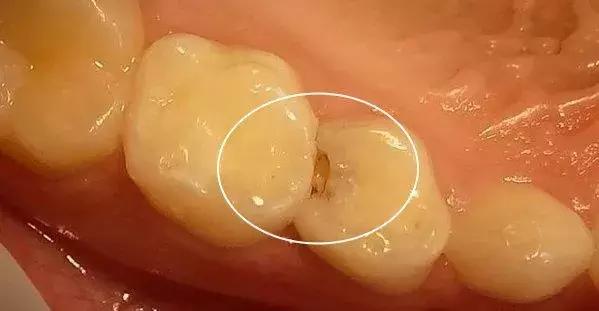

为什么两牙之间会容易蛀牙?

两颗牙齿接触的地方,看似密不可分,但它们之间其实是存在着间隙的。这些间隙很窄,你可能用肉眼看不出来。

同样地,因为间隙太窄,以至于你用牙刷都无法有效地清洁干净。

如果这些区域长期没有得到有效的清洁,细菌就会在里面扎堆生长,这最后的结果,很可能就会演变成蛀牙。